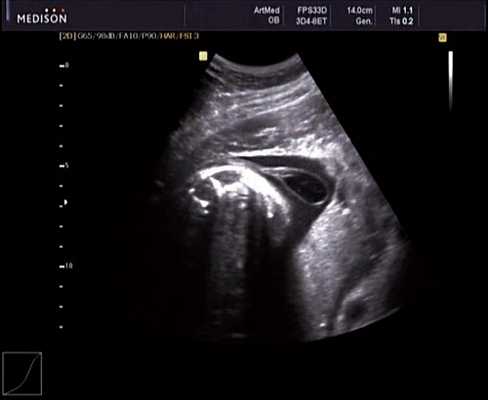

Беременная М., 21 года. Впервые обратилась в клинику в срок 20 нед беременности. Исследование проводилось на аппарате SonoAce-R7 (Samsung Medison) с использованием режима поверхностной объемной реконструкции 3D/4D. При изучении позвоночника плода в трех плоскостях костных деформаций не выявлено. В грудном отделе позвоночника обнаружено тонкостенное кистозное образование с анэхогенным содержимым, стебельчатой формы (рис. 10-12). Степень "прозрачности" содержимого была выше околоплодных вод, что позволяло идентифицировать его как ликвор. В проекции грыжевого выпячивания располагалась петля пуповины, дифференциальную диагностику которой без труда удалось провести с помощью ЦДК (рис. 13).

У плода наблюдалась выраженная гидроцефалия, обусловленная синдромом Аронольда - Киари II (рис. 14, 15).

Рис. 14. Беременность 20 нед. Гидроцефалия.

Рис. 15. Беременность 20 нед. Удлинение ножек мозга и вклинение мозжечка в затылочное отверстие при синдроме Арнольда - Киари II.

Учитывая типичную форму грыжевого выпячивания и отсутствие элементов нервной ткани, было высказано предположение о наличии у плода менингоцеле (рис. 16). Женщина приняла решение о прерывании беременности.

Рис. 16. Беременность 20 нед. Менингоцеле размером 37х21 мм.